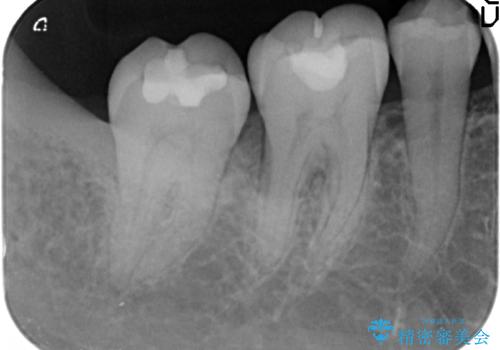

X線検査、歯周組織検査より歯の周囲の骨が溶ける歯周病であることがわかりました。

歯を抜かずに残せるよう、再生療法・歯周ポケット除去手術を計画します。